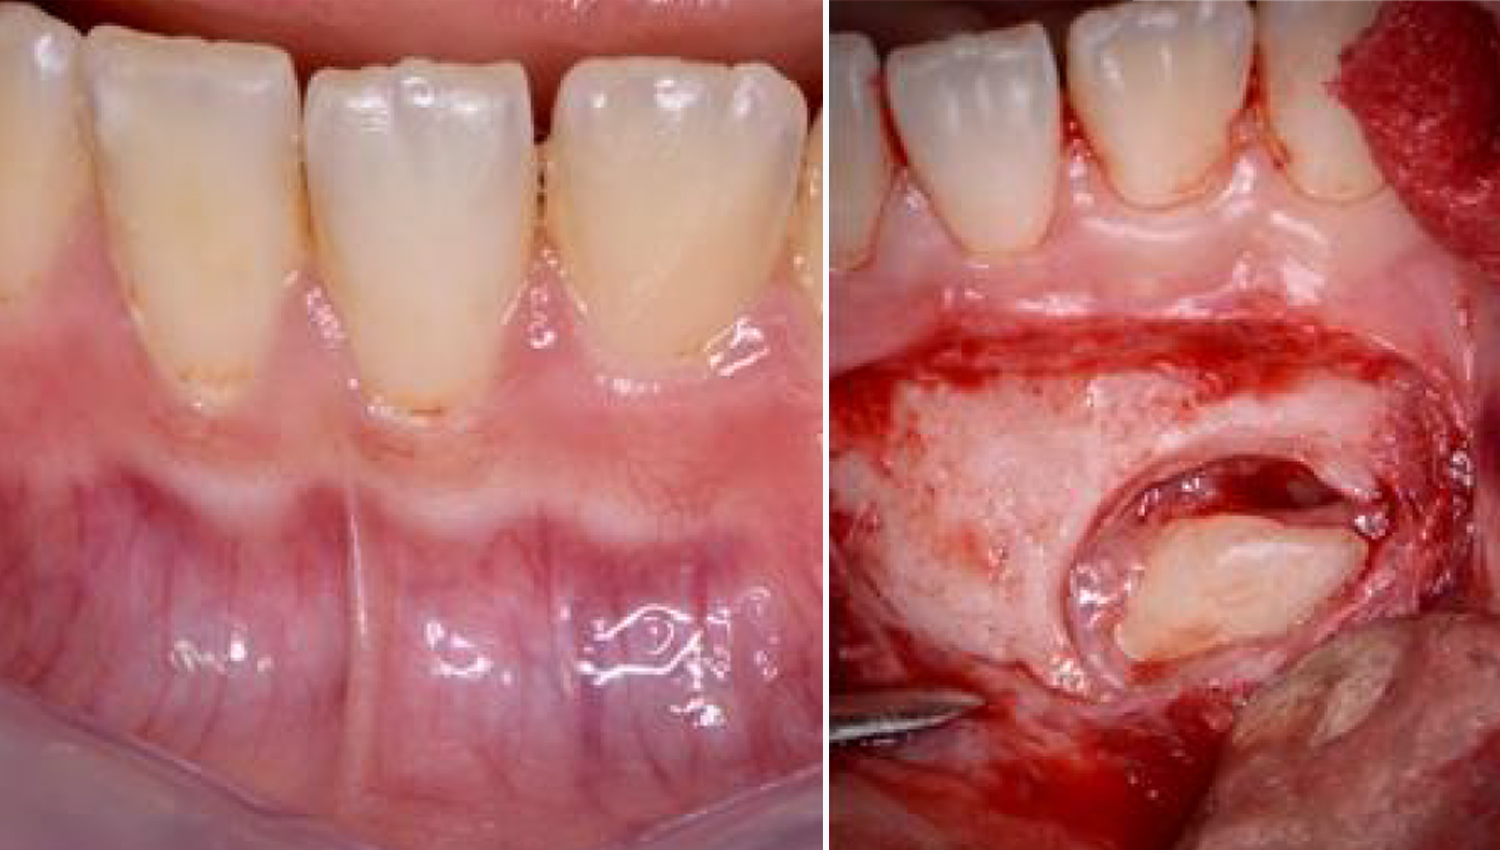

2.Surgical extraction of the impacted 43.

3.The bone defect was thoroughly debrided of all soft tssues and curretted with sharp Lucas hand currettes. Powerbone Dental Putty was used to graft the site, in order to assist and accelerate bone healing prior to initiating othodontic treatment.

4.4. The Bone defect filled with Powerbone Dental Putty. No barrier membranes were used (left picture). The sectioned impacted tooth after removal (right picture).